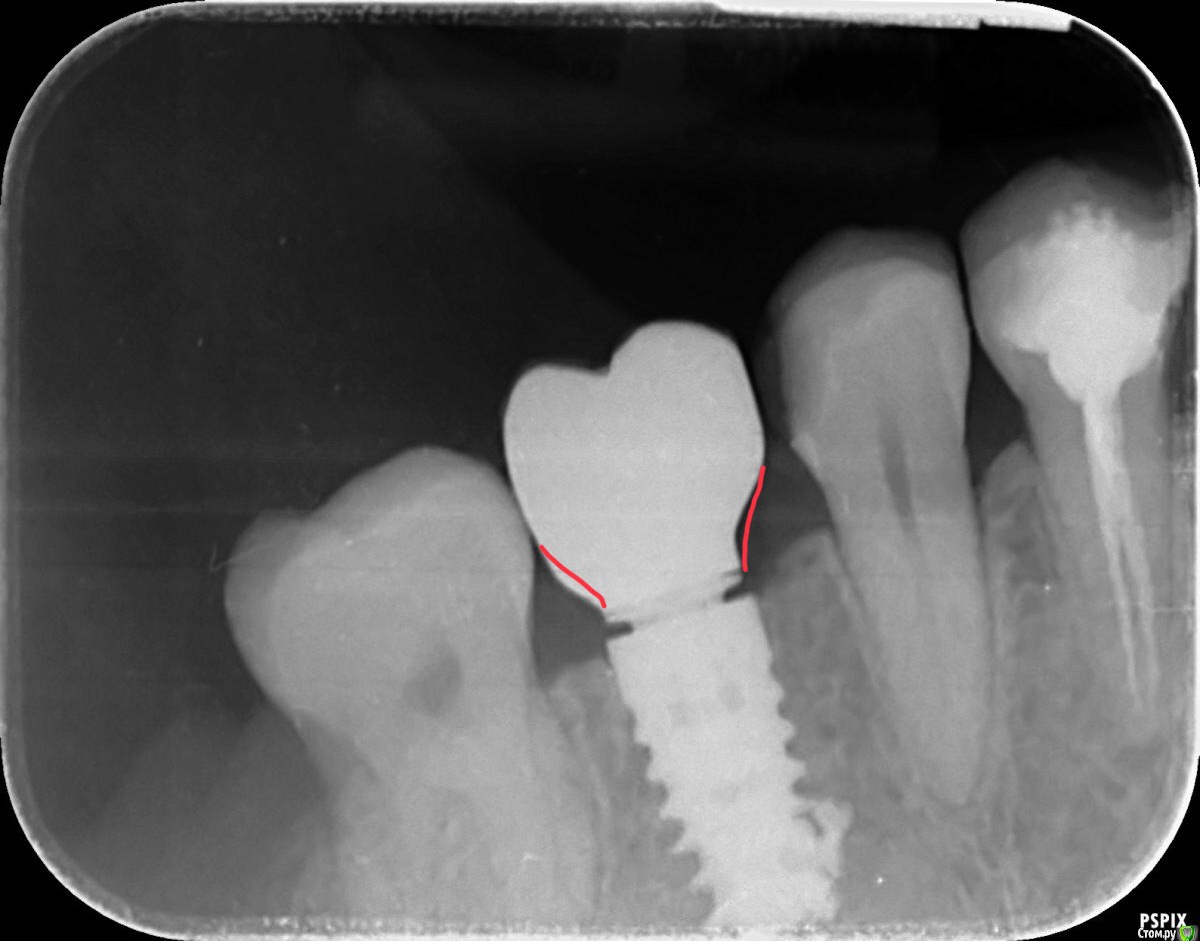

nabuhiko Опубликовано 12 марта, 2020 Поделиться Опубликовано 12 марта, 2020 Перый раз столкнулся с этой системой, имплант ставили не у нас в клинике со слов пациентки (тоже стоматолог) размер 5х10 с конусом. Купил трансфер снял оттиск получил коронку на винтовой фиксации, проверил контактные пункты (не мешают) а на контрольном снимке платформа не достает до импланта около 30-40 микрон. Десна тоже не мешает, кость тоже... в чем может быть причина или это нормально для этой системы? Ссылка на комментарий

АнтонТЛТ Опубликовано 13 марта, 2020 Поделиться Опубликовано 13 марта, 2020 Переключение платформ это.Коронка не досажена до титанового основания, отклеится может. Профиль прорезывания не совсем верно сделан. Ссылка на комментарий